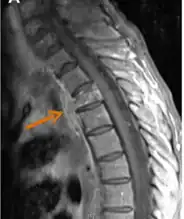

Contrast-enhanced magnetic resonance images showing contiguous spread of pulmonary actinomycosis to the spine